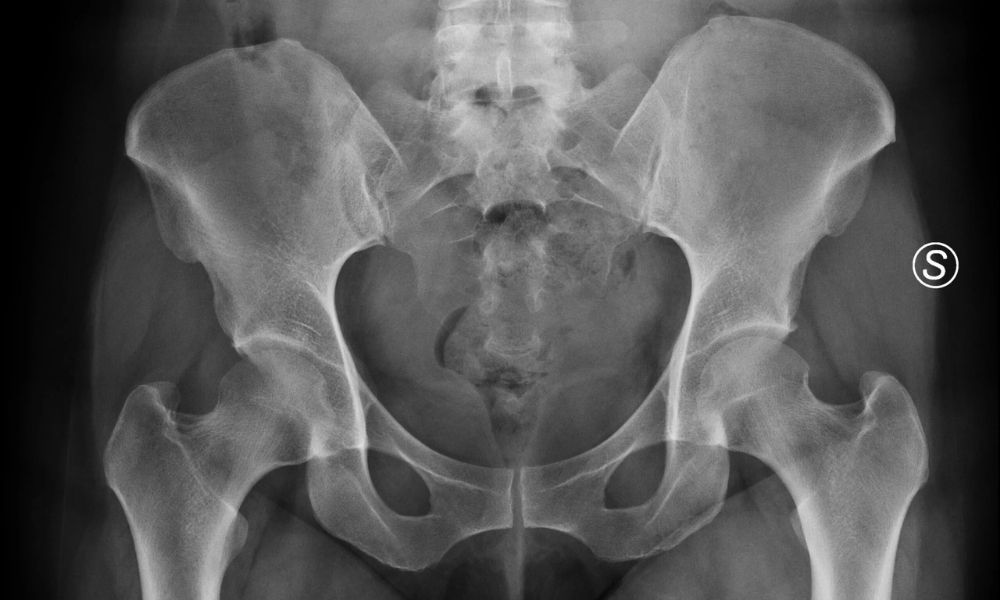

Femoral anteversiyon tanısında yürüme analizi önemli bir araçtır. Hastanın yürüyüşü özel kameralar ve sensörlerle kaydedilerek detaylı incelenir. Bu analiz sayesinde kalça rotasyonu ve içe basma derecesi ölçülür. Kesin tanı için görüntüleme yöntemleri de devreye girer. MR ve BT taramalarıyla femur kemiğinin kalçaya göre açısı belirlenir. Normal açının 10–15 derece olması beklenir; 20 derece üzeri anormal kabul edilir.

Görüntüleme sonuçlarıyla femur başı ve boynu arasındaki açılar ölçülür. Bu ölçümler anteversiyonun şiddetini ortaya koyar. Hafif, orta veya ileri düzey olarak sınıflandırılır. Diğer yürüme bozukluklarıyla karışmaması için ayırıcı tanı yapılır. Kalça çıkığı, serebral palsi ya da tibial torsiyon gibi durumlar dışlanmalıdır. Bu nedenle kapsamlı değerlendirme gerekir.